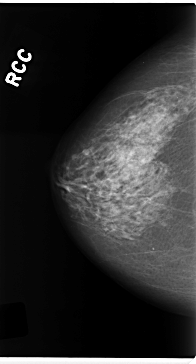

C_0224_1.RIGHT_CC

RIGHT_CC LINES 4720 PIXELS_PER_LINE 2544 BITS_PER_PIXEL 12 RESOLUTION 50 NON_OVERLAY